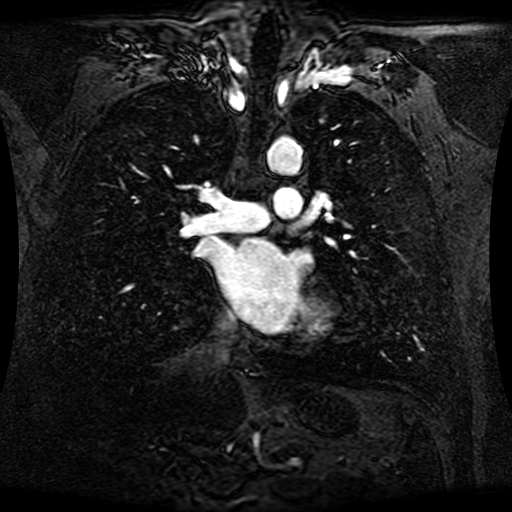

These magnetic resonance angiography (MRA) images show coronal slices acquired from consecutive anteroposterior positions within the torso. The study was performed on a 1.5T General Electric (GE) Signa imaging system with gadolinium-contrast-enhancement for visualization of the cardiopulmonary vasculature. The pulse sequence used was a 3D time-of-flight fast spoiled gradient recalled acquisition in steady state (FSPGR, TR=6.3, TE=1.4, NEX=1, FOV = 40cm, slice thickness = 1.2mm).

This sample image contains 76 frames. It is available in DICOM format (E1154S7I.dcm), as an animated GIF (E1154S7I.gif), as .ogg, .mp4, .webm, and .swf animations (one of which is shown above), or as individual PNG-format frames (see below).